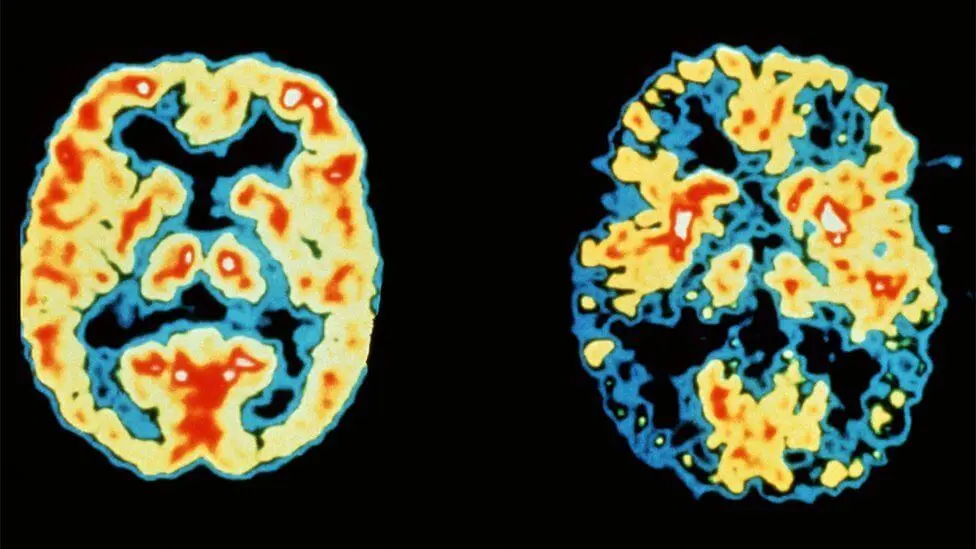

Above:A 68-year-old woman with a 10-year history of cognitive impairment showed marked hypometabolism with a pattern suggestive of Alzheimer's disease prior to PET scan, PET scan after treatment with inhibitor (RI). Gradually approaching the normal brain, the patient's cognitive ability improved significantly.